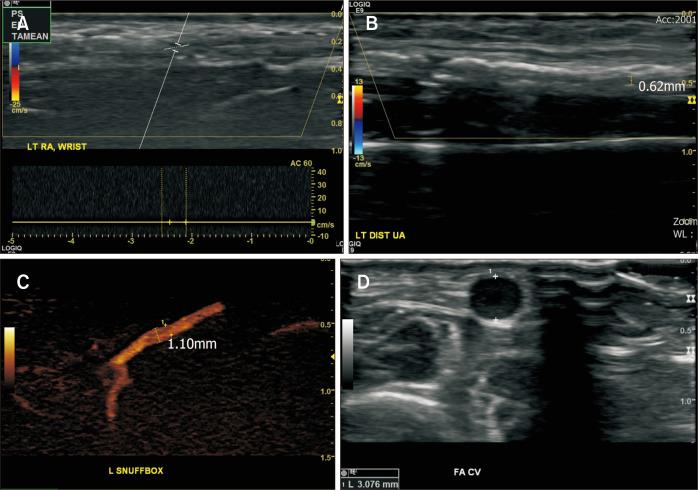

用于终末期肾病肢体挽救的鼻烟壶内肱动脉至桡动脉原位旁路术

In Situ Bypass from the Brachial to Radial Artery in the Anatomical Snuffbox for Limb Salvage in End-Stage Renal Disease.

Diabetes and renal failure frequently involved in small vessel arteriopathy. With medical advancements, those patients survive longer with an increasing incidence of resultant arterial occlusive disease affecting the distal upper extremity (UE). In patients with ulcers or gangrene in the distal UE, bypass surgery is often complicated by severe atherosclerosis with calcification, resulting in poor distal anastomosis quality. Here we report a patient with a fingertip gangrene who were successfully treated with in situ bypass from the brachial artery below the elbow to the radial artery in the anatomical snuffbox under local anesthesia. Bypass graft patency was maintained during the 18-month follow-up. If the forearm cephalic vein and radial artery in the anatomical snuffbox are of adequate quality, in situ bypass to radial artery in the anatomical snuffbox may be a useful option for limb salvage in selected patients.

摘要

糖尿病和肾衰竭常伴有小血管动脉病变。随着医学的进步,这些患者存活时间更长,导致影响上肢远端(UE)的动脉闭塞性疾病的发病率不断上升。在患有上肢远端溃疡或坏疽的患者中,旁路手术常因严重的动脉粥样硬化伴钙化而复杂化,导致远端吻合质量差。在此,我们报告一例指尖坏疽患者,在局部麻醉下成功进行了从肘部以下肱动脉到鼻烟壶部桡动脉的原位旁路手术。在18个月的随访期间,旁路移植血管保持通畅。如果前臂头静脉和鼻烟壶部桡动脉质量足够,对选定患者进行鼻烟壶部桡动脉原位旁路手术可能是挽救肢体的有用选择。